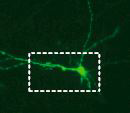

The rapidly induced human neurons became functionally integrated into circuitry when transplanted into mouse brain.

Source: Thomas Südhof, M.D., Stanford University